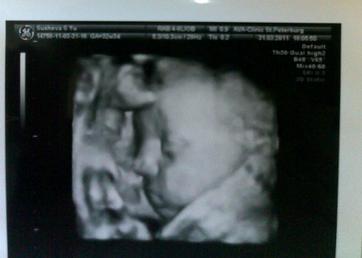

УЗИшечки-3 )

Сходили мы с маленькой на УЗИ)Доктор говорит,что всё хорошо,очень крупными не будем,пока прогнозируют примерно 3300-3400гр при рождении)По-моему,это довольно нормальный вес,да и не в кого нам очень большими быть)Сейчас весим 1869гр)Рост не сказали)Воды в нормальном количестве,плацента толщиной 32мм, I-II степени зрелости (соответствует сроку), гипоксии нет. ПДР ставят 25 мая)) Лежим головой вниз,обвитий нет,ттт..)

А еще доктор сказал,что у нас длинные волосы..Не знаю как он увидел это на УЗИ,но попытался мне показать))Я не увидела,честно говоря) И надутые щёчки))Щечки увидела)

Вот последнее фото)Лежим пяткой у лба))

Да,это 3д)На самом деле,видно неплохо,но на экране было лучше,просто сложно поймать момент было,потому что она всё время пряталась)поэтому немножко смазалось и не видно какие у нас милые губки)))